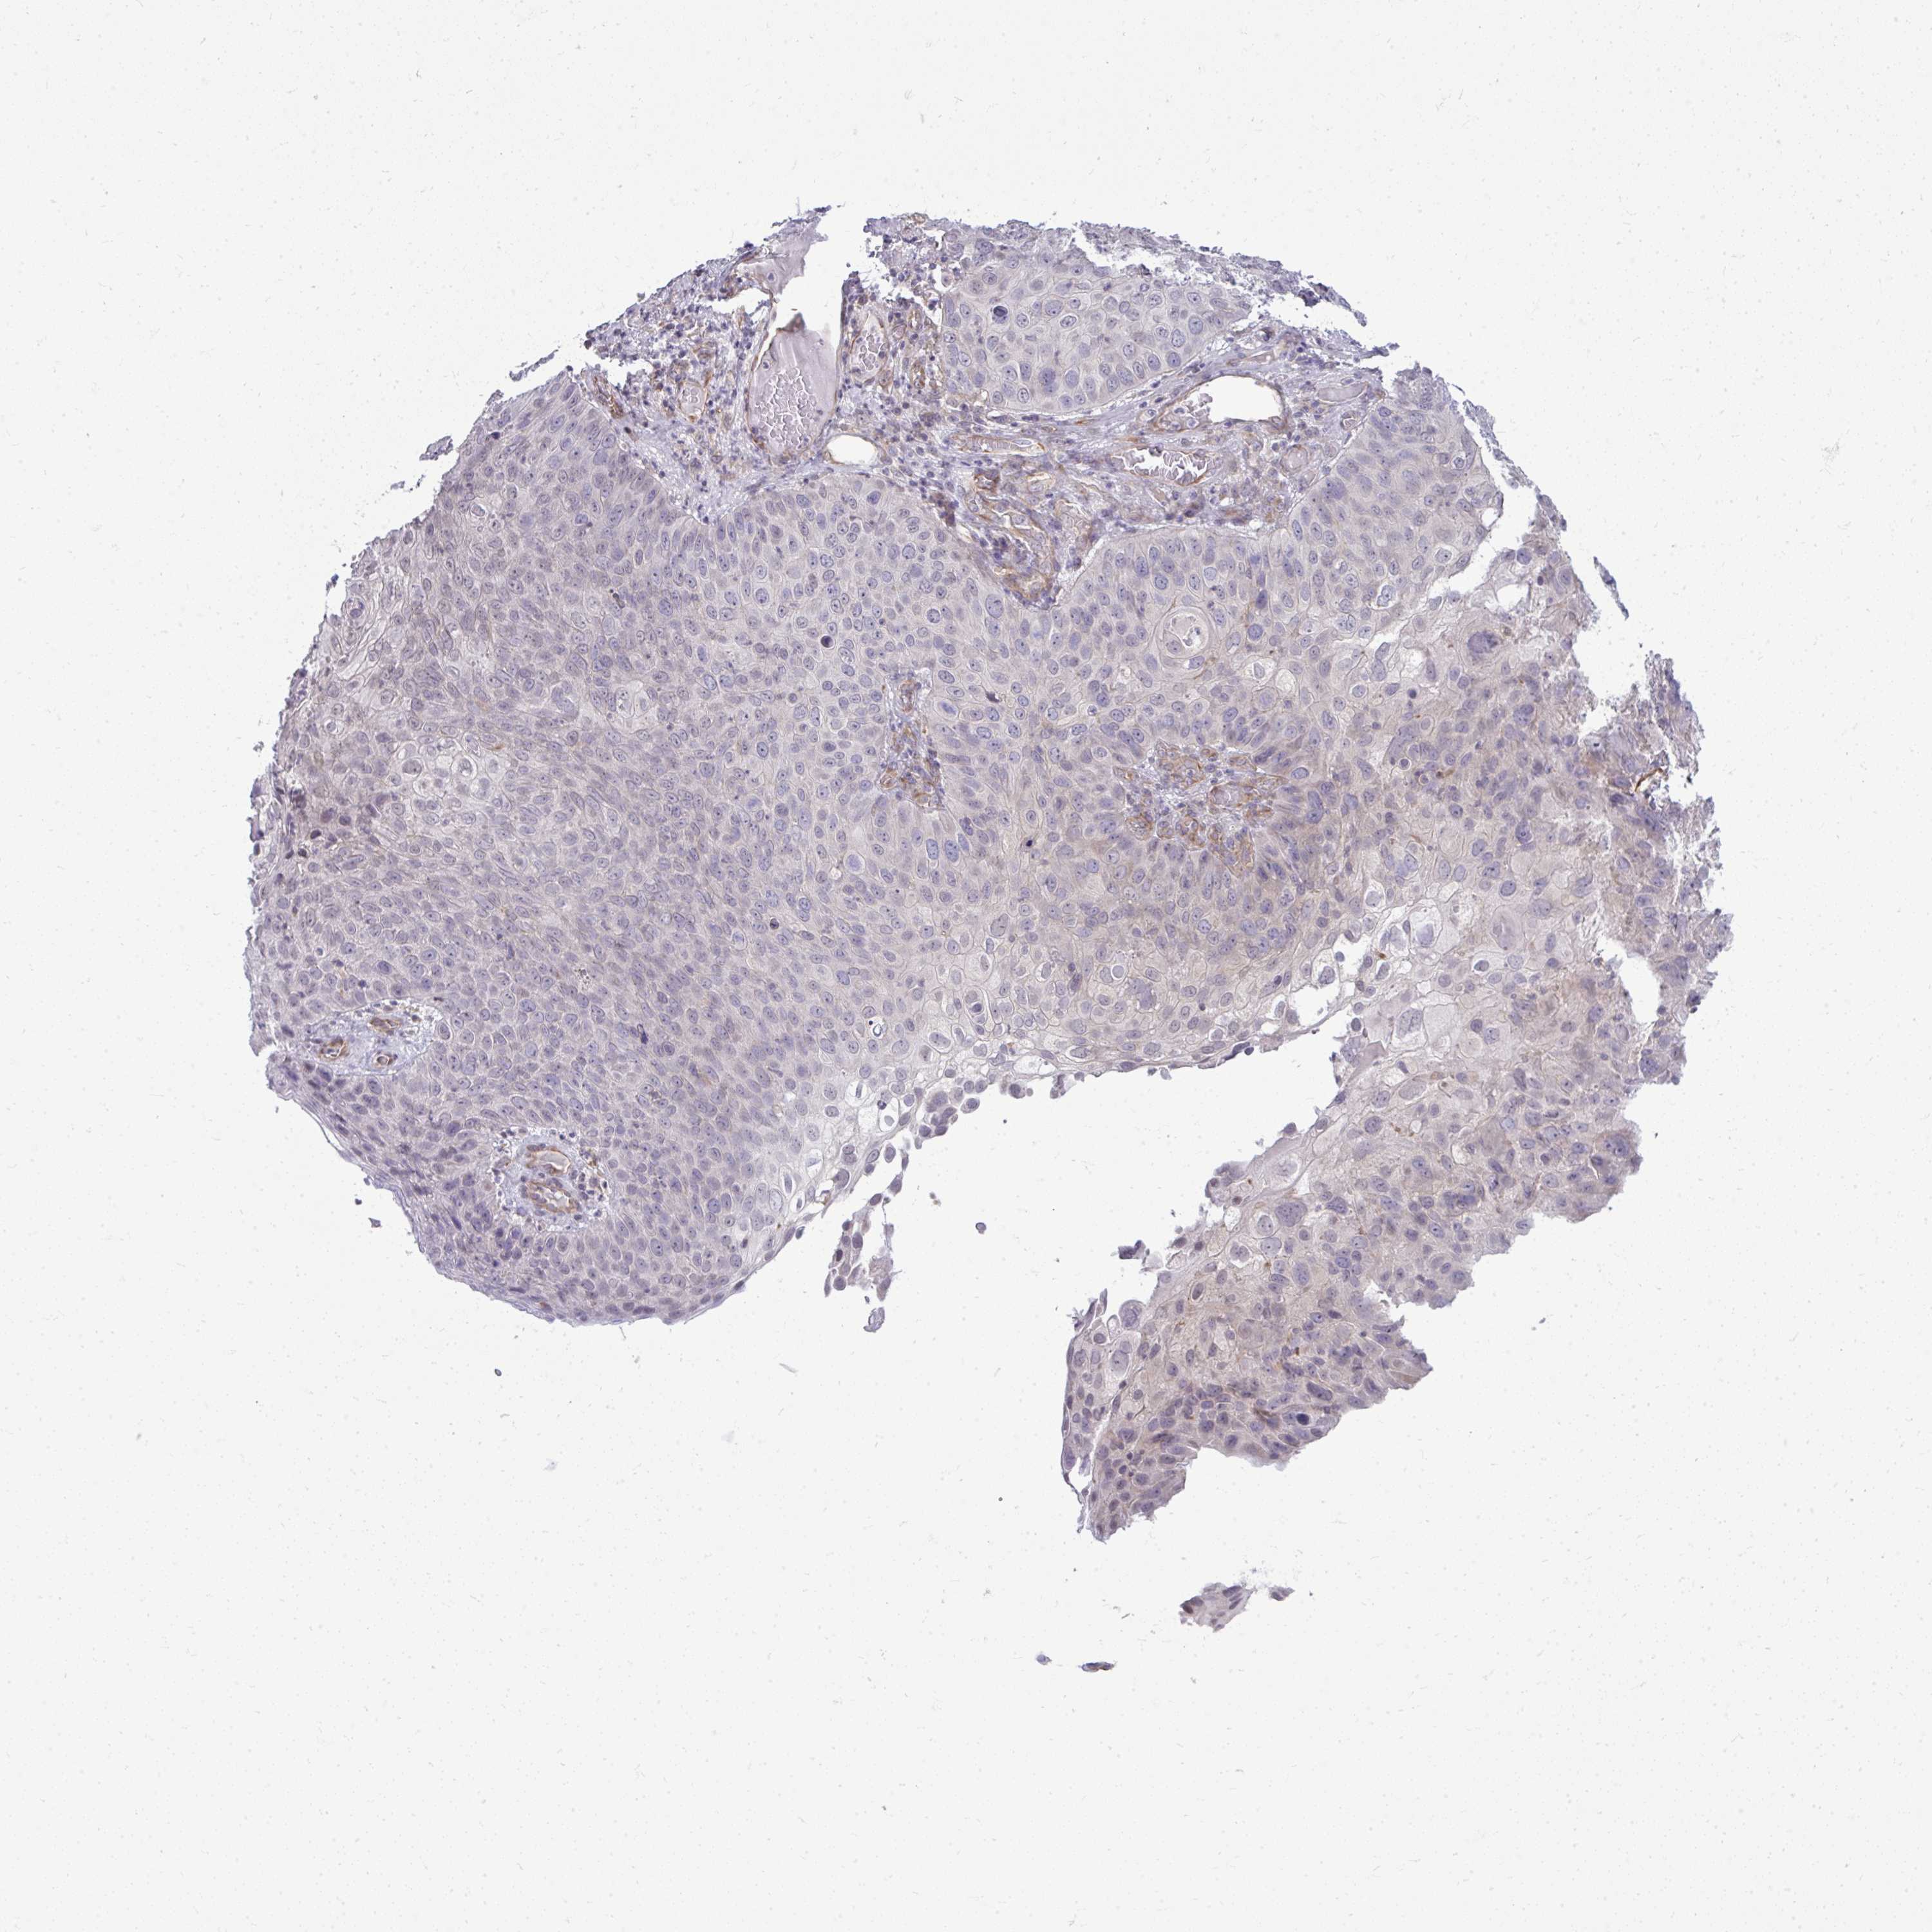

SKIN CANCER - Protein expressioni

A mouse-over function shows sample information and annotation data. Click on an image to view it in a full screen mode. Samples can be filtered based on level of antibody staining by selecting one or several of the following categories: high, medium, low and not detected. The assay and annotation is described here.

Antibody stainingi

Antibody staining in the annotated cell types in the current human tissue is reported as not detected, low, medium, or high, based on conventional immunohistochemistry profiling in selected tissues. This score is based on the combination of the staining intensity and fraction of stained cells.

Each image is clickable and will lead to virtual microscopy that enables deeper exploration of all samples and also displays staining intensity scores, fraction scores and subcellular localization as well as patient and tissue information for each sample.

Antibody HPA053970

Antibody HPA058655

Staining

High

Medium

Low

Not detected

Intensity

Strong

Moderate

Weak

Negative

Quantity

>75%

75%-25%

<25%

None

Location

Nuclear

Cytoplasmic/membranous

Cytoplasmic/membranous,nuclear

Basal cell carcinoma

Squamous cell carcinoma, NOS